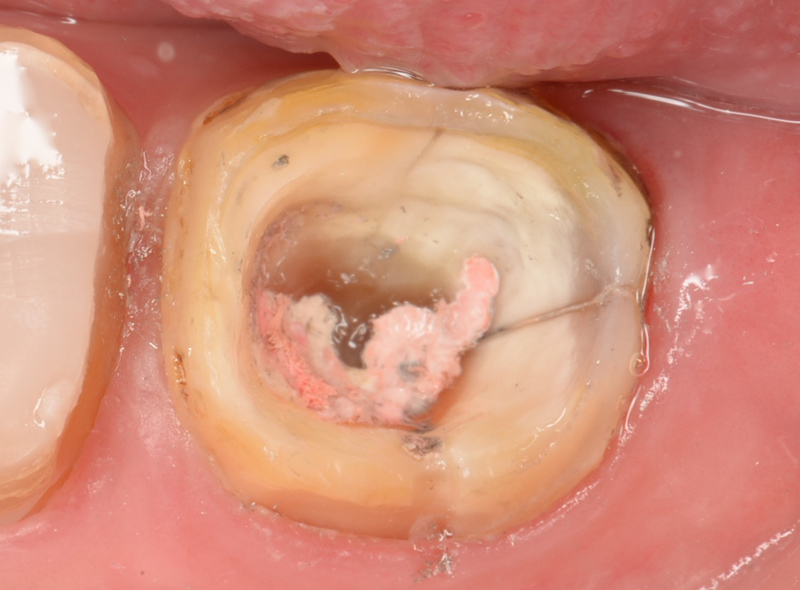

歯を削って、神経部分である歯髄を露出させ取り出します。

歯髄を「ファイル」と呼ばれる器具で除去、さらに根管内の神経も取り除きます。

奥歯の場合、神経が複雑になっているので、他の歯よりも時間がかかってしまいます。

マイクロスコープとは歯科用顕微鏡ともいわれるもので、「肉眼」よりも数十倍(最大80倍)視野を拡大してくれる装置です。つまり肉眼では確認できない部位までを見ることができます。

下の画像は肉眼とマイクロスコープの見え方の違いです。

これだけの違いがあります。

目に見えない小さいものを見えるようにして行う治療と指の感覚でなんとなく行う治療ではどちらが正確で精密な治療が行えるかは一目瞭然かと思います。